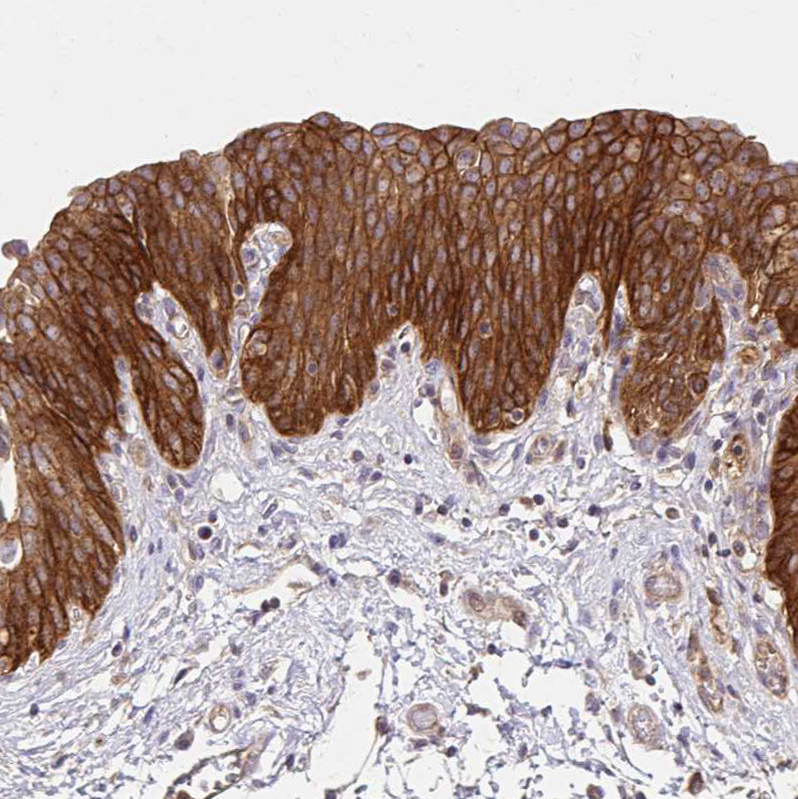

Immunohistochemical staining of human endometrium, rectum, skin and urinary bladder using Anti-ITGA2 antibody HPA060991 (A) shows similar protein distribution across tissues to independent antibody HPA063556 (B).